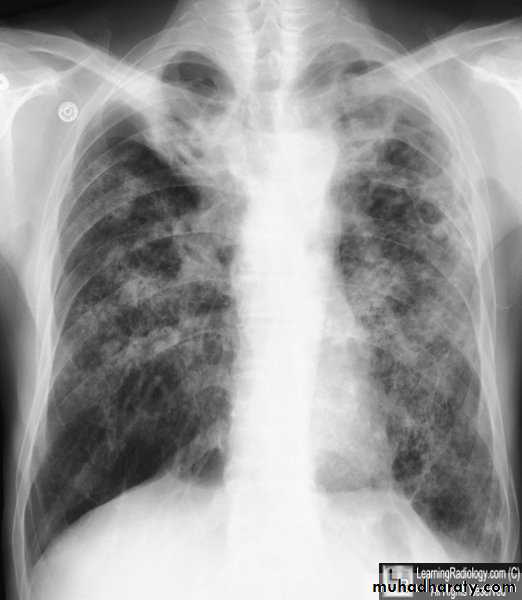

Miliary TBBilateral diffuse tiney nodules1-3 mm in diameter uniform in size and uniformly distributed involve whole lung fields.

miliary TB